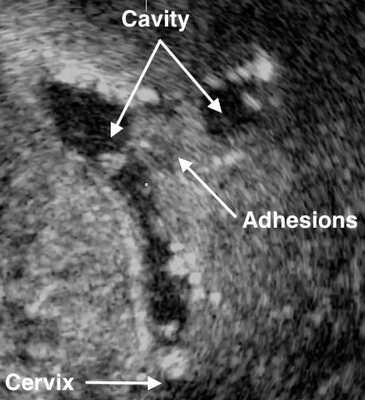

- Ультразвуковое исследование. Если есть спайки, то на снимках видны эхогенные, нерегулярные эксцентричные линейные сигналы — беловатые плотные участки рубцовой ткани или локальное истончение эндометрия. Исследование проводят в лютеиновую фазу (период с момента овуляции и до начала менструаций).

- Соногистерография — ультразвуковое исследование, во время которого в полость матки вводят физиологический раствор.